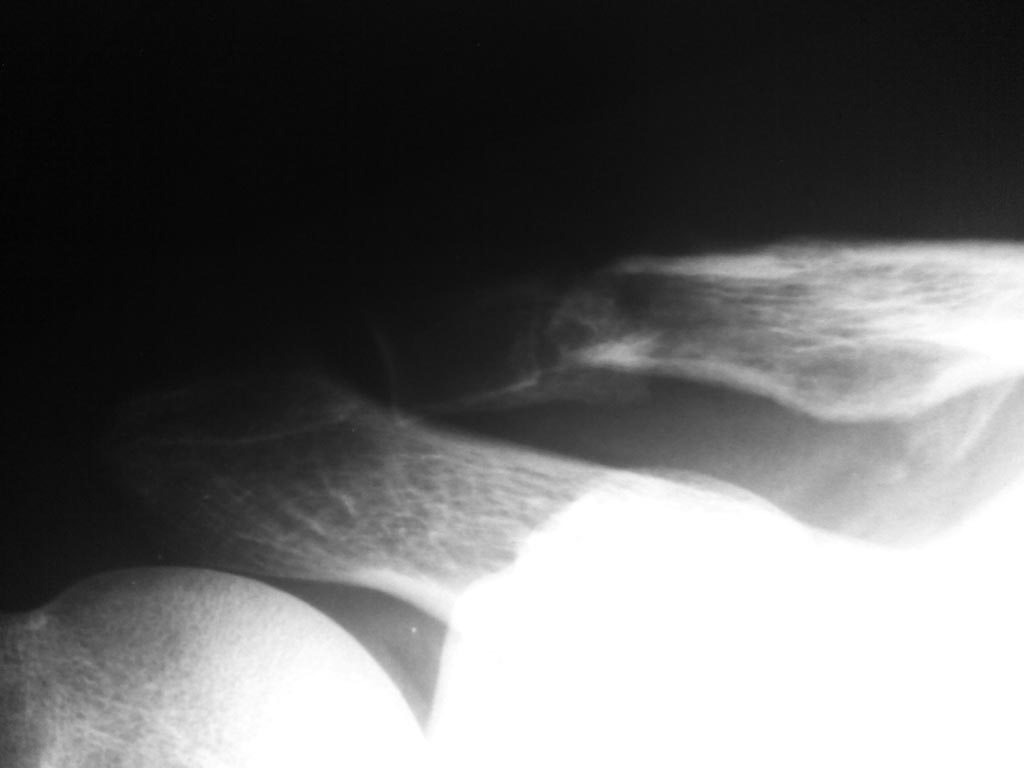

Доброго времени суток коллеги. Хочется узнать Ваше мнение о данном

случае. 10 июня травма - падение. В травмпункте диагностирован перелом

акромиального конца ключицы. Лечение выполнялось консервативно,

иммобилизация 5 недель. В ноябре выполнен контрольный Rg снимок в связи

с болью при занятии спортом. Клинически: движения в плечевом суставе в

полном объеме, безболезненные. При пальпации проксимальный отломок

смещен кзади на 5 мм, пальпация безболезненная. На Rg: ложный сустав

акромиального конца ключицы. Какова дальнейшая тактика лечения на ваш

взгляд?